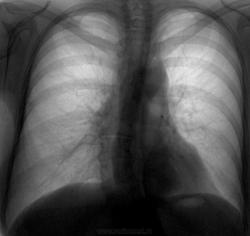

"Читая" вчера флюорограф, при просмотре данного случая опять вспомнил высказывания кого-то из коллег о якобы перебитых цифровых флгр. ОГК, мол позвоночник виден - значит потеряны детали легочного рисунка. Доброкачественное образование левого легкого, подтв. КТ, на протяжении 5 лет без динамики (столько работает у нас цифр.флгр.). Судя по всему давнее, но обратили внимание с первой цифровой флгр. Поднимали пленочный архив - там на фоне сердечной тени оно не диф.